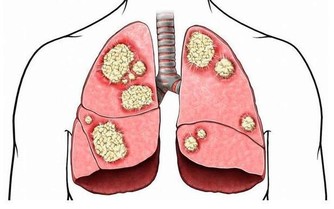

就在近些日子裡,美國已經將幽門螺桿菌列為明確致癌物,而幽門螺桿菌的感染情況,在全球範圍內都是比較嚴重的,只是發展中的國家會更為突出,中國的感染率就很高,已經超出了50%,由此可以知道,中國幽門螺桿菌感染人群較多,而幽門螺桿菌與癌症之間關係密切,為防止更多人感染幽門螺桿菌,需要清楚知道為什麼被感染,怎樣預防?

新興社會的到來,讓大家過上好日子了,同時,也讓很多人養成了大量的惡習,在眾多惡習之下,很容易引發一些問題,幽門螺桿菌感染率變高,就是其中一個問題。人體內有很多菌群,有些是有益菌,有些是不好的細菌,幽門螺桿菌就是一個極壞的細菌,對胃黏膜造成的損傷也很大,且攻擊性極強,繁殖力也很厲害,不及時的治療,就可能誘發癌症。

但不得不說,多數被感染的人群,都是需要治療的,因為胃部情況並不良好,對於已經出現消化性潰瘍和慢性胃炎的人,或者說家裡有過胃癌病史的人,還是需要及時進行治療的,以免給胃部帶來更大的傷害。